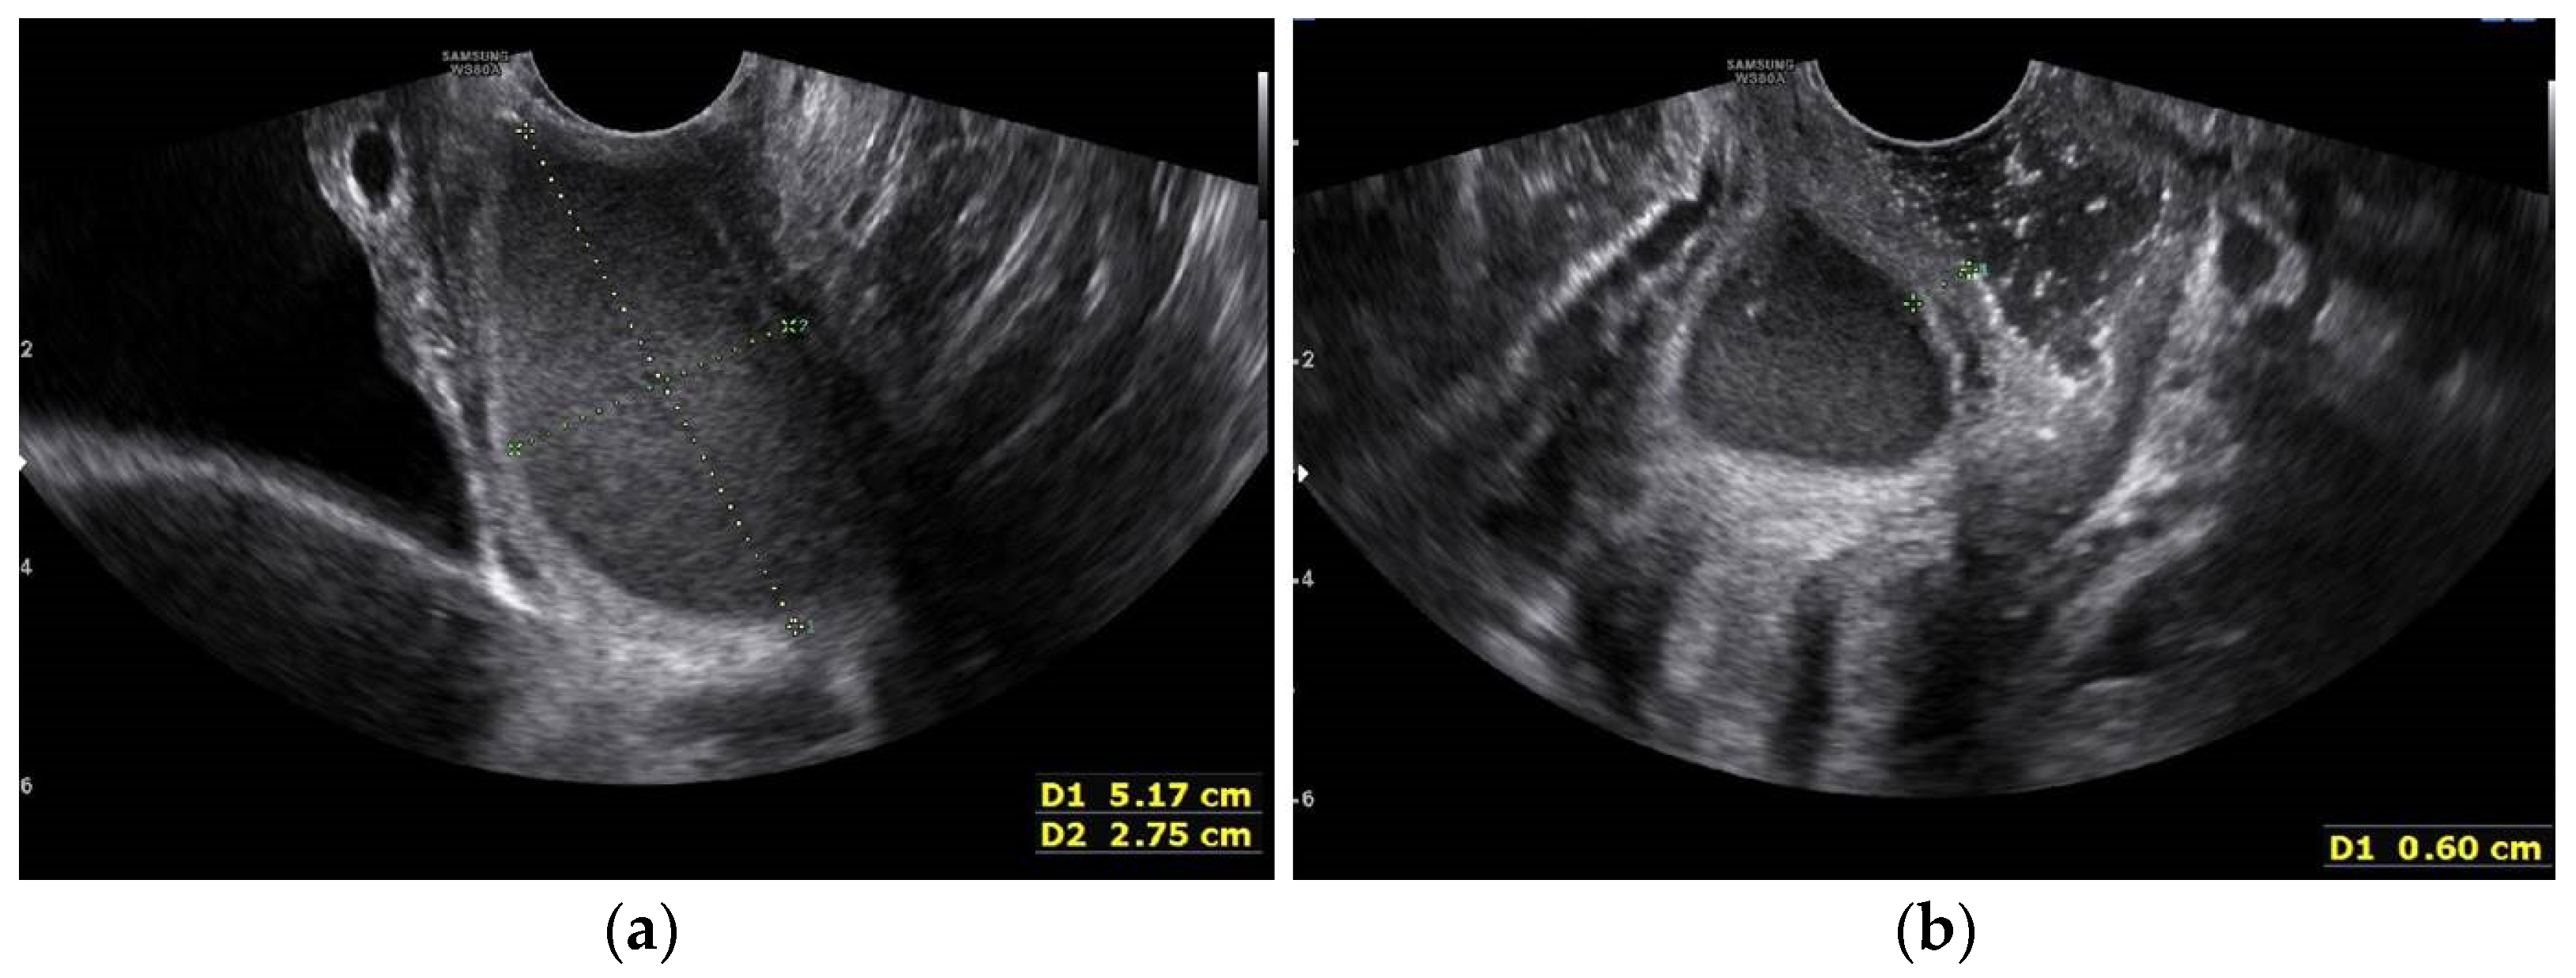

One month later, three days before the planned operation, the patient again visited ER due to severe lower pelvic pain. This time we were able to identify the bulging vaginal wall using a vaginal speculum exam and transvaginal USG (Figure 6a,b).

Figure 6.

Transvaginal USG image one month after the initial visit. (a) More substantial fluid collection in the right side obstructed hemi-vagina; (b) Transvaginal ultrasonogram image showing the thickness of the vaginal septum to be approximately 6 mmn (measured with +calipers).